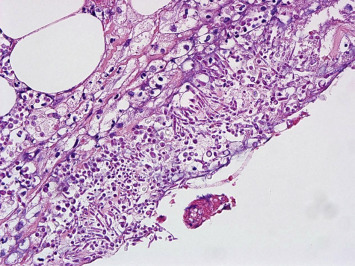

An emergency operation was performed, and multiple perforations from the ascending colon to the rectum, significant pus debris at the peritoneum, and massive dirty ascites were discovered. Amebic trophozoites (Fig. 5), CMV inclusion bodies (Fig. 6), and fungal hyphae (Fig. 7) were identified in the resected colon specimen. Broad-spectrum antibiotics with an antifungal agent were prescribed. Serum tests showed positive IHA for amoeba, and a CMV viral load of 272,000 cp/mL. The ascites culture yielded Enterococcus faecium, Candida albicans, and Candida krusei. The pleural effusion culture yielded Aspergillus fumigatus. Despite aggressive medical treatment, his condition deteriorated gradually, and he passed away about 10 weeks after admission.

Figure 5. Microscopic view of the resected specimen showing amebic trophozoites at the site of the colon ulcers. |

An endoscopic finding of HIV enteropathy may mimic the features of IBD and lead to misdiagnosis. In patients with advanced HIV infection, CD4 T-cell count depletion and opportunistic infections (OIs) occurs. OIs include bacterial, viral, fungal, and protozoan infections. CMV is the most common opportunistic pathogen in HIV-infected patients and can involve the whole gastrointestinal (GI) tract. Eosinophilic nuclear inclusions are characteristic of CMV-infected cells and are usually found in stromal and endothelial cells [6]. Entamoeba histolytica infections are usually asymptomatic; however, in immunocompromised patients, invasive amebiasis has mostly presented as colitis and liver abscesses. The trophozoite invades the colonic mucosa and spreads to the extra-intestinal organs. Endoscopy is useful in diagnosing amebic colitis, since amebic trophozoites can be detected from the biopsy [7]. The most common fungal infection in immunocompromised patients is candidal esophagitis; however, enteric fungal infections are unusual, even in HIV-infected patients. The diagnosis was based on fungal hyphae noted in the biopsy specimen. Highly active antiretroviral therapy (HAART) decreased the incidence and prevalence of OIs.

We reviewed the patients previous data, endoscopic findings, and histological results. Neither typical, continuous, and confluent mucosal inflammation, ulcerations, granularity, nor loss of visible vascular pattern of the mucosa were present. The initial pathology report revealed the presence of ulcers with focal crypt abscesses, which were nonspecific features of colitis. Furthermore, when the slides were reviewed again, the initial biopsy revealed the presence of amebic trophozoites. Therefore, if the slides had been examined in more detail, the correct diagnosis may have been made earlier.